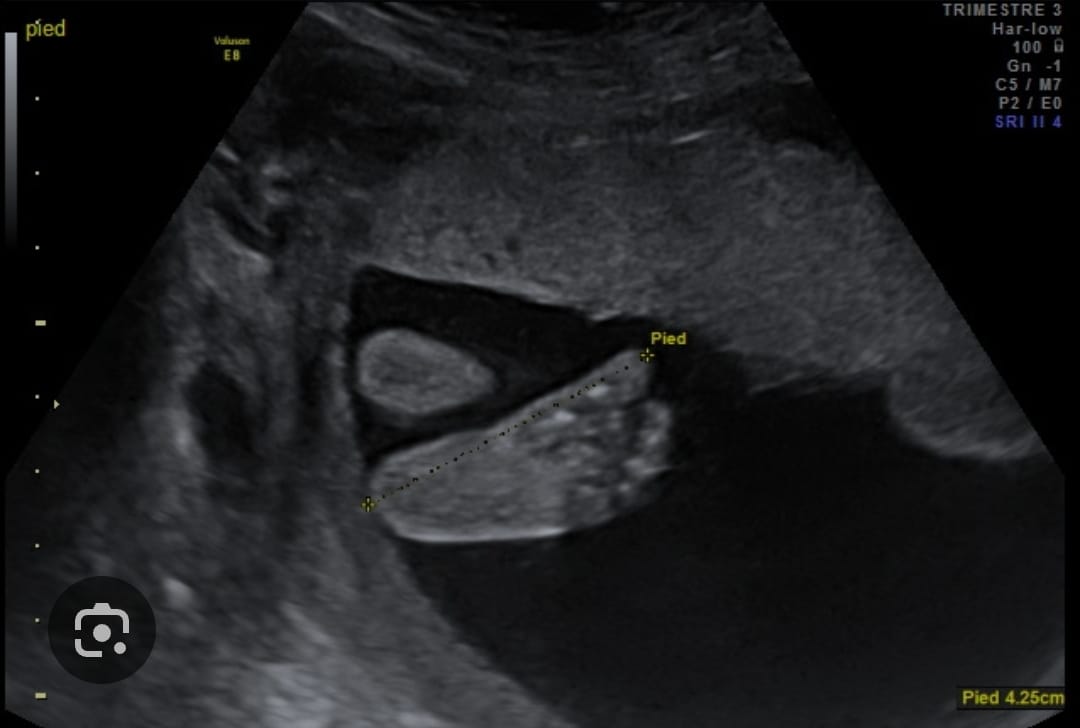

Ci-dessous quelques images de ce que l’on peut observer à la T2 :